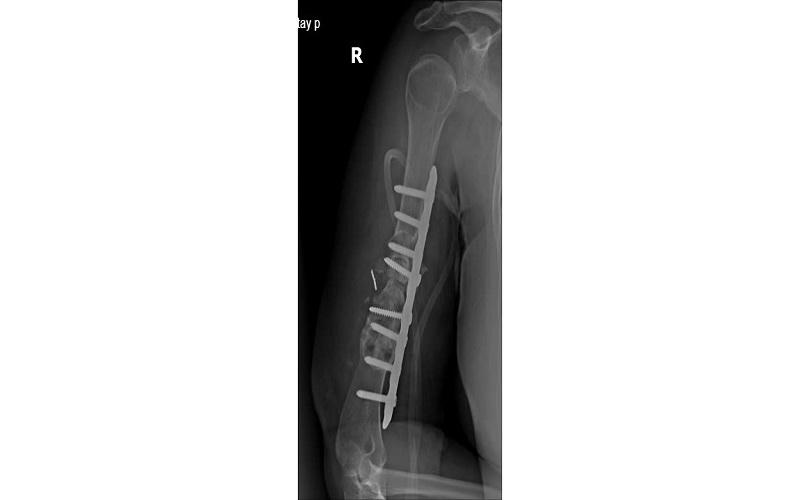

Ngày 18/5/2025, với sự đồng thuận của người bệnh và gia đình, ca phẫu thuật được tiến hành, các bác sĩ tháo bỏ phương tiện kết hợp xương cũ, nạo sạch và làm mới ổ gãy, lấy xương cánh chậu ghép vào ổ gãy, cố định xương bằng nẹp khóa. Sau khoảng 90 phút ca phẫu thuật đã hoàn thành.

Tình trạng bệnh nhân sau khi mổ. |